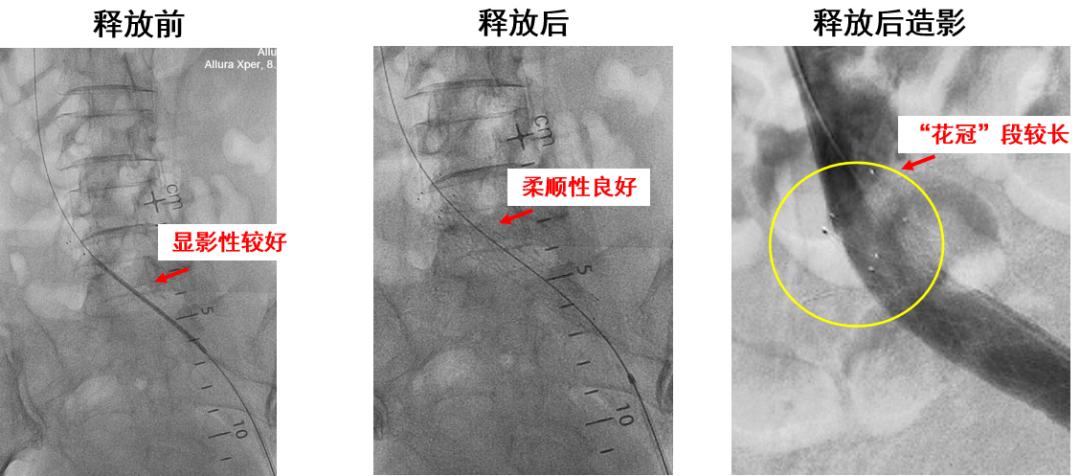

产品E:病例一(定位准确,柔顺性好)

显影性能较好,定位精准

锥形支架设计,贴合血管解剖结构和形态